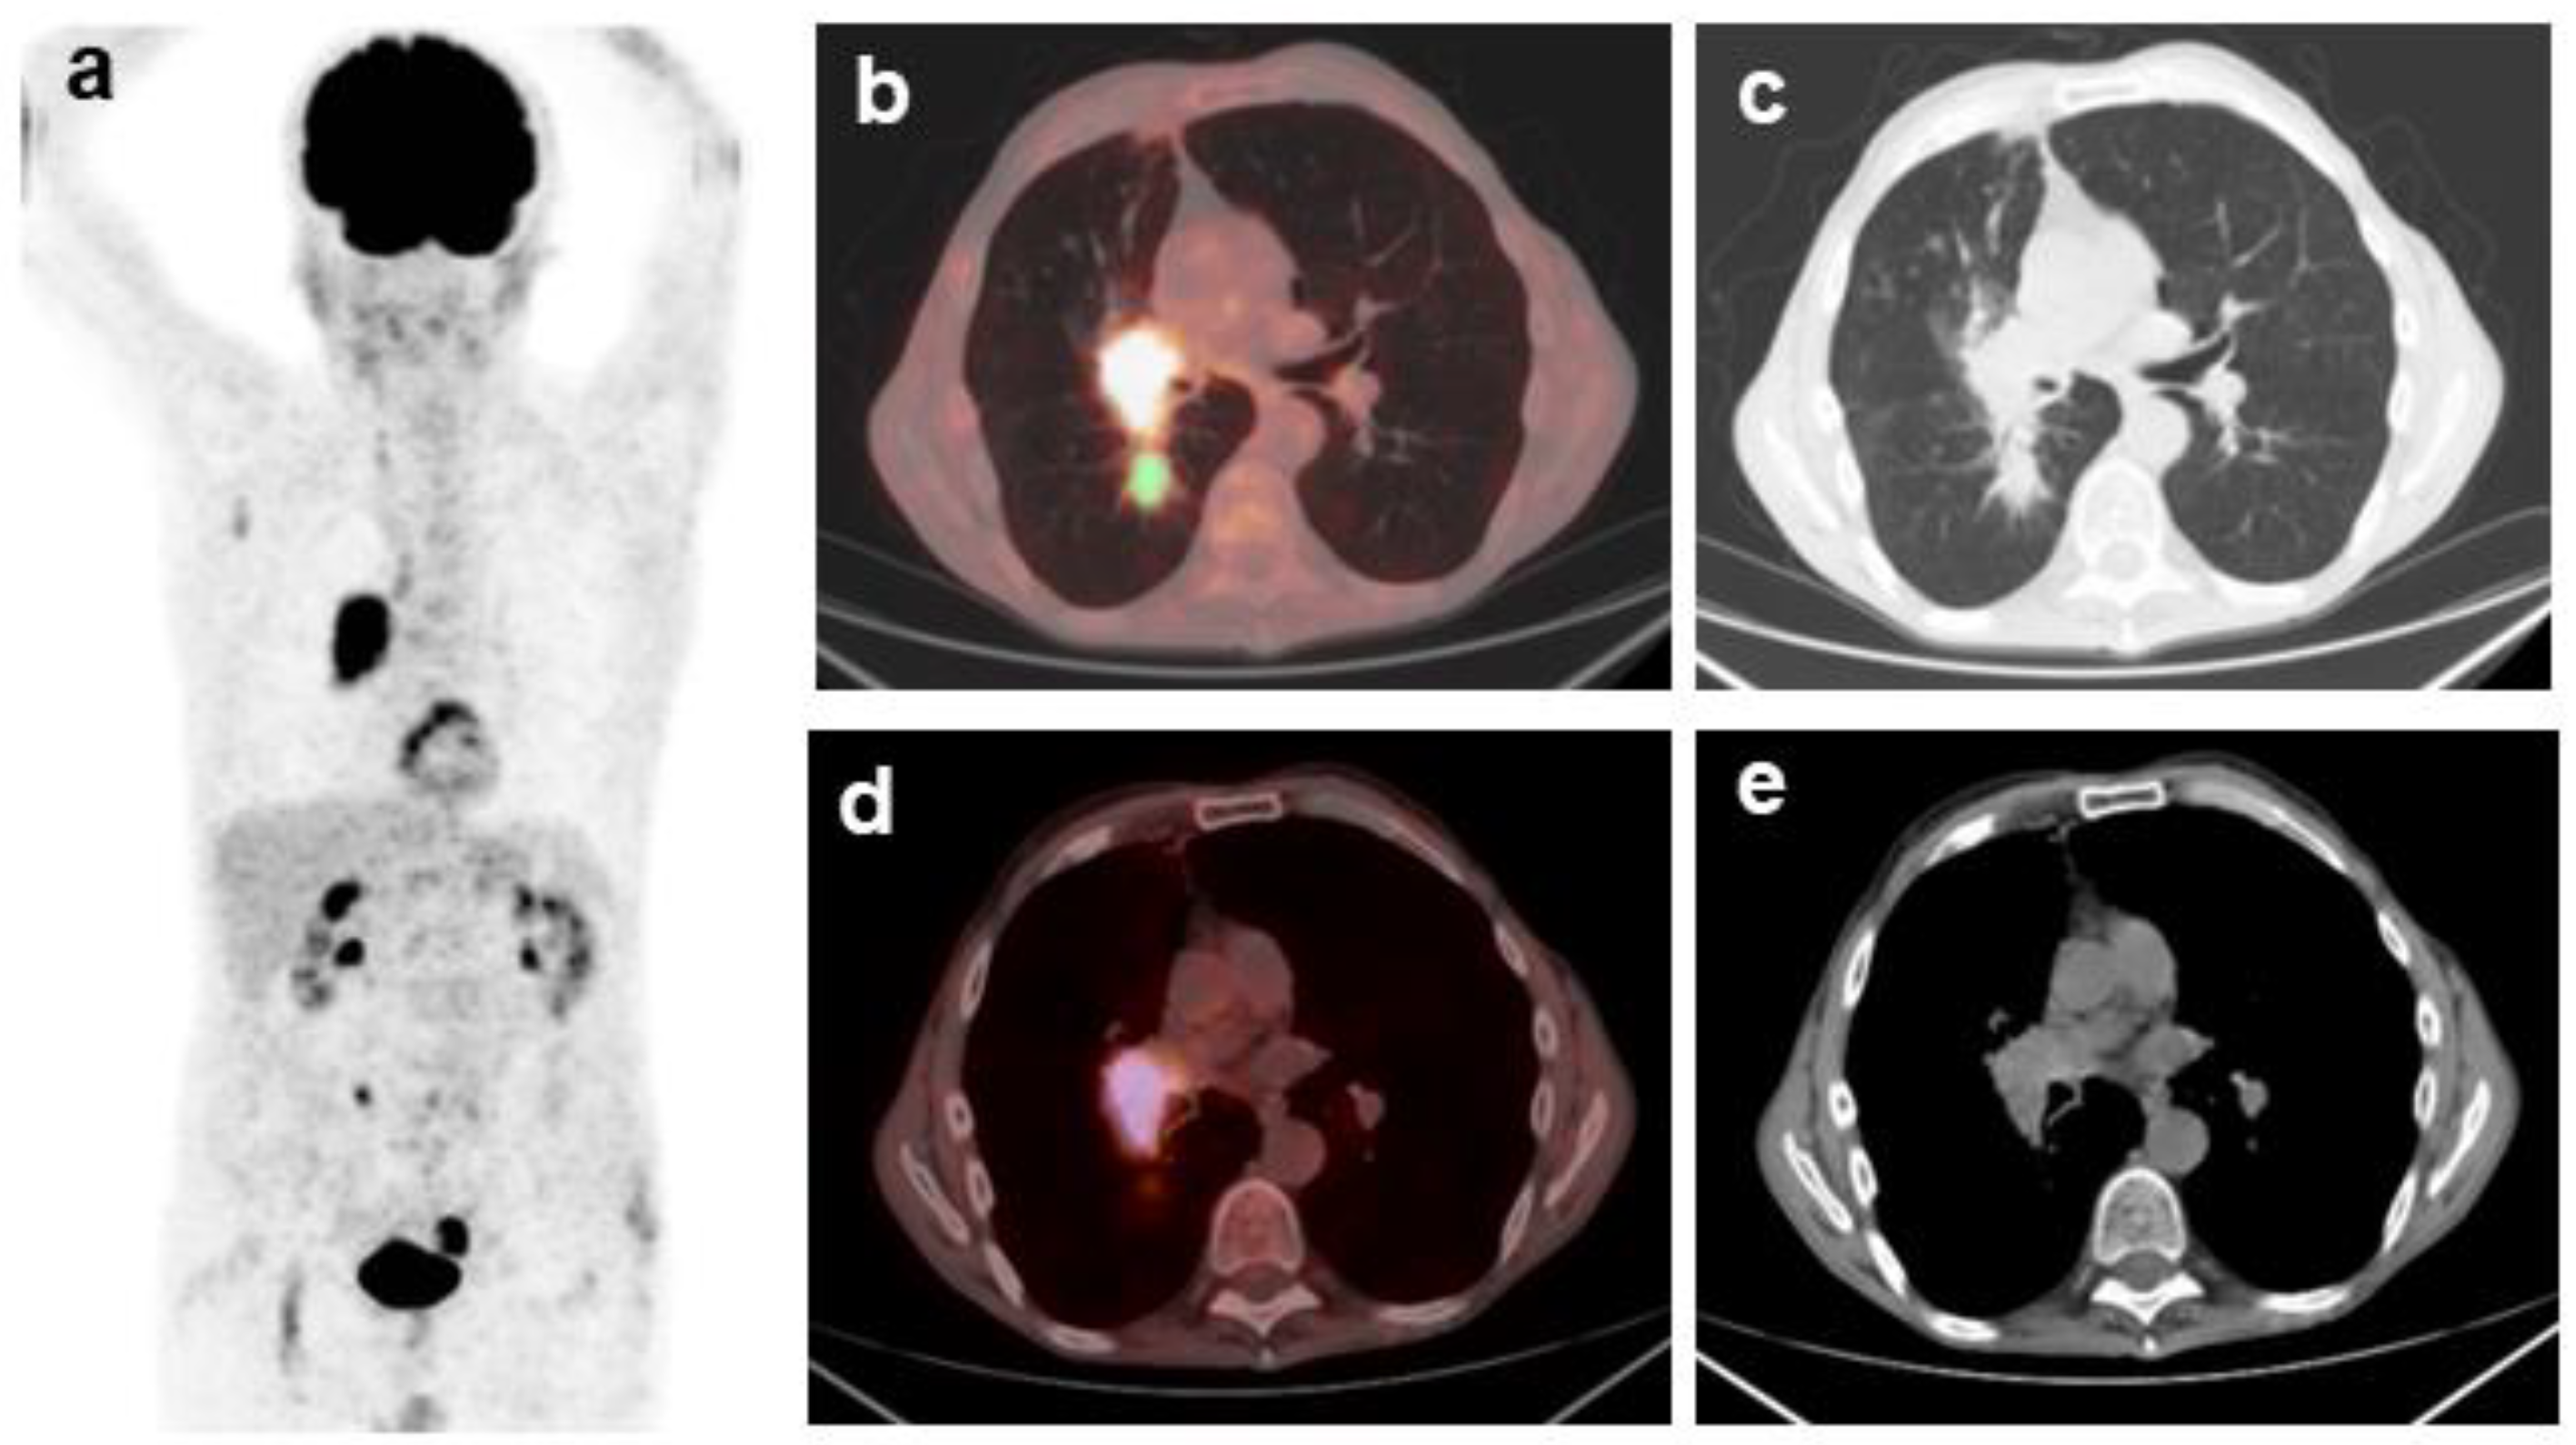

Although CoV of targeted lymph nodes was not an independent prognostic factor for OS, we combined it with the CoV value determined on the corresponding primary tumor and tested whether the four possible combinations could better stratify our population. A statistically significant difference among the four survival curves (χ2 = 10.7245, p = 0.0133) was found via Kaplan–Meier analysis using the combined thresholds of CoV. In particular, patients with CoV of targeted lymph nodes ≤ 0.29 and CoV of primary tumors > 0.38 had the best prognosis (median OS = 28 months) (Figure 3).

Figure 4 shows representative 18F-FDG PET/CT images of patients with the best prognosis, having CoV of targeted lymph nodes ≤ 0.29 and CoV of primary tumors > 0.38 (Figure 4a), and patients with the worst prognosis, having CoV of targeted lymph nodes > 0.29 and CoV of primary tumors ≤ 0.38 (Figure 4b).

Figure 4. Representative 18F-FDG PET/CT fusion images of a patient of the best prognosis group (a), based on the combination of CoV N ≤ 0.29 with CoV T > 0.38, and a patient of the worst prognosis group (b), based on the combination of CoV N > 0.29 with CoV T ≤ 0.38. The color bar indicates 18F-FDG uptake.